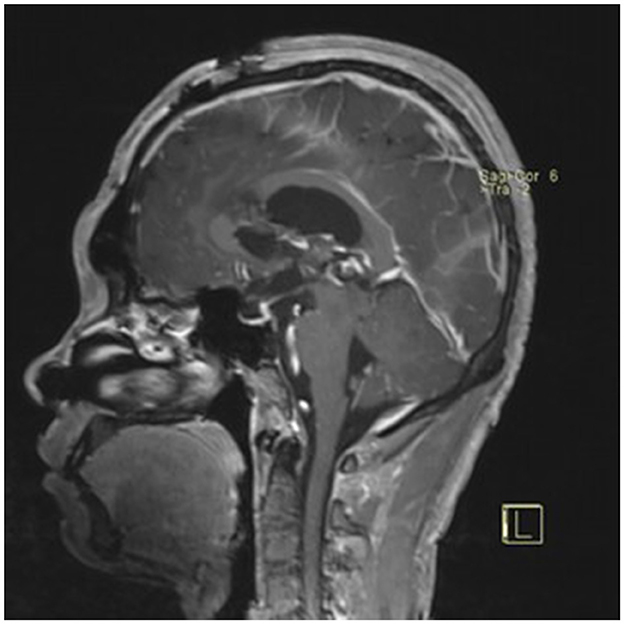

A 22-year-old male presented with intermittent dizziness and headache lasting for 2 weeks. MRI at admission revealed a cystic mass in the pineal region, accompanied by supratentorial hydrocephalus (Figures 3–5). No surgical contraindications were identified. After discussion with the patient's family, neuroendoscopic resection was performed via the Transfrontal-Transventricular-Transforaminal Approach. Intraoperatively, a 20 × 20 mm soft, well-vascularized tumor was found obstructing the cerebral aqueduct. The lesion had well-defined margins and was carefully dissected from surrounding adhesions, preserving adjacent veins and brain tissue. Macroscopic total resection was achieved en bloc (Figures 6–8). Postoperative day 1 MRI confirmed complete tumor removal and resolution of hydrocephalus (Figures 9–11). Postoperatively, no complications were observed. However, due to personal reasons, the patient was discharged on postoperative day 11. Histopathology confirmed a mixed germinoma. No recurrence or surgery-related complications were noted during follow-up.

Preoperative contrast-enhanced MRI (sagittal view) showing the pineal region tumor.

Figure 5

Preoperative contrast-enhanced MRI (coronal view) showing the pineal region tumor.